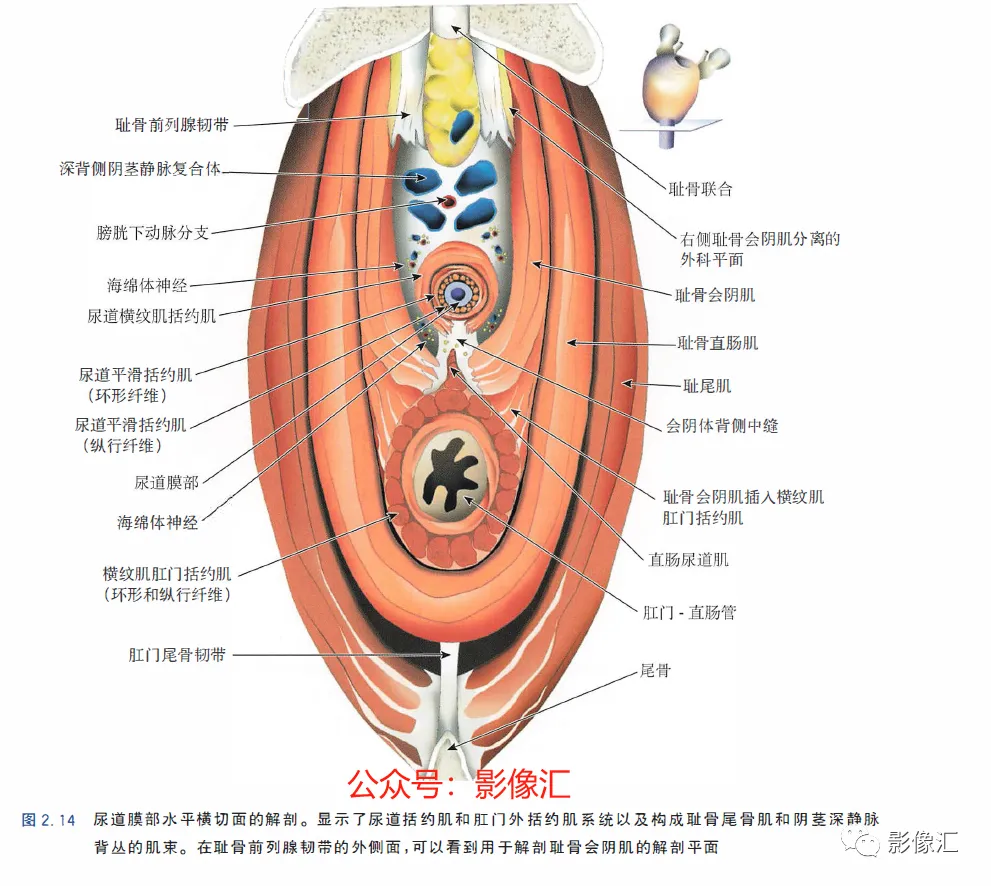

前列腺尖部是用于表示前列腺腺体尾侧(最下方)的术语,与尿道膜部密切接触。前列腺尖部可显示出不同的形态:圆环形或腹侧,背侧或两侧突出(图2. 9和图2.10) ,了解前列腺尖部形态的重要性主要在于两点:(1)前列腺尖部或多或少与EUS(尿道膜部的横纹肌纤维)头侧区域重叠(或覆盖),这些纤维部分融入前列腺尖部(图2.11)。在接受根治性前列腺切除术的患者中,有必要采用能够外翻(exteriorising)和解剖这部分横纹肌纤维的手术技术, 以保持控尿功能(图2.12)。(2)在根治性前列腺切除术中必须避免阳性边缘 。值得注意的是,在尖部水平,腺体组织仅为外周带组织,尖部仅前缘一小部分为AFMS。此外,前列腺尖部构成所谓的梯形区域的顶部,这是众所周知的解剖薄弱区域,在该区域前列腺癌可更易侵犯至前列腺间隙(图2.8)。在其前外侧,前列腺尖部由外括约肌群覆盖,与AFMS及从膀胱颈延伸来的由平滑肌构成的逼尿肌群相融合(图2. 13)。前列腺尖部尾侧与尿道膜部起始部相延续。男性的尿道膜部被认为是位于前列腺尖部和尿道球部之间的尿道部分,长度约为1cm。其内有尿道内括约肌(IUS)和尿道外括约肌(EUS)。IUS从膀胱颈(此处最厚)延伸到尿道球部,沿尾侧方向厚度逐渐减小。IUS环尿道膜部,由双层平滑肌纤维组成,包括内层纵行肌和外部的环形肌(图2. 13和图2. 14)。IUS的神经支配来自自主神经、交感神经和副交感神经系统。下腹下神经丛负责前列腺、前列腺尖部和尿道膜部的所有自主神经支配。其终末支沿内侧走行达耻骨上肌,外侧走行达尿道膜部的EUS,在腹侧构成所谓的阴茎海绵体神经(负责勃起机制)和尿道海绵体神经(负责尿道膜部黏膜的自主神经传入,直接与控尿机制有关(图2 . 13 和图2. 14)。EUS构成横纹肌平面(横纹肌纤维),在尿道膜部水平围绕IUS,在前列腺尖部的前外侧上扩展,并在该水平上构成所谓的EUS围裙(图2. 13)。其肌纤维主要是I 型(即没有肌梭),尽管强度低,但专门负责长时间收缩。EUS的功能在于排尿间期保持尿道腔塌陷,从而防止无意识的尿液渗漏。EUS最厚处位于尿道膜部水平,厚度向头侧逐渐减小,最终构成前列腺围裙。该围裙以Ω(希腊字母“欧米伽”)形围绕尿道膜部,而后正中不包绕, 形成“后正中脊”(图2. 13 和图2. 14)。此外,EUS的部分横纹肌纤维融入到前列腺尖部的下部,位于精阜下方,融入纤维的多少依赖于前列腺尖部形态(图2. 11) 。EUS的神经支配和动脉供血分别来自外阴神经和外阴内动脉。该神经为躯体神经,因此EUS可随意控制。外阴内神经和动脉均向头侧走行,至会阴深横肌处,发出分支支配EUS最尾侧部分,随后形成阴茎背侧神经脊背侧动脉。前列腺尖部与支配EUS的外阴内动脉的分支之间距离为3~13mm (图2. 13)。IUS和EUS构成所谓的控尿被动及内在因素。它们的功能基本上是“塌陷”尿道至“后正中脊”,这样可防止排尿间期无意识的尿液“泄露”(图2.11和2.13)。阴茎海绵体神经在前列腺周围筋膜的后外侧及前外侧走行。手术操作时保留这些外侧神经对于确保前列腺根治术后勃起功能的恢复是至关重要的。会阴体是一纤维肌性结构,难以在解剖上进行评估,其功能是支持所有构成会阴部及支撑盆腔脏器的肌肉及腱膜结构。对于控尿,会阴体形成一固定的底盘,通过将EUS的横纹肌平面压至底盘处,从而可使EUS正确发挥功能,这样在排尿间期可以正确地使尿道塌陷。会阴体由以下结构组成(图2.13)和图2.14)。

肛提肌与尿失禁的外在因素(主动因素)相关。肛提肌由两个肌肉平面组成,即耻尾肌和髂尾肌。耻尾肌起源于耻骨的中分支(mid-branch of the pubis),在肛尾韧带和尾骨的水平从背侧插入。耻尾肌的内侧纤维向内走行,在肛门直肠管的水平处构成肛门外括约肌后面的环,让直肠形成一定弯曲,有助于肛门压力和闭合机制。同时,耻骨直肠肌的内侧纤维向尾部中线移动,在尿道膜部以及前列腺尖部及其括约肌系统外侧走行,并在会阴体、肛门外括约肌的最深部分和尿道球部水平插入。这些肌肉纤维被称为耻骨会阴肌(也称为耻骨尿道肌或前列腺提肌)。耻骨会阴肌构成会阴底部的腹内侧部分,并且最终可以覆盖耻骨前列腺韧带的外侧表面,使得其更远端的纤维沿着平行于尿道膜部的平面走行。在大多数情况下,要完整保留这个肌肉平面。要求部分分离耻骨前列腺韧带,目的是可以找到正确的解剖平面进行手术切除(图2. 15)。MRI在评估前列腺尖部、尿道膜部和尿道括约肌复合体中的作用

根治性前列腺手术有两个主要目标:完全切除肿瘤和令人满意的术后功能,即控尿及阴茎勃起功能的恢复。为了在根治性前列腺切除术后实现早期控尿恢复,需要完全保留尿道括约肌系统,同时保留耻骨直肠肌和耻骨会阴肌(后者更为重要)。EUS的保存始于在腺体顶端前外侧上彻底分离EUS裙,向尾部方向操作。根据尿道周围筋膜,可正确识别和分离尿道膜部的EUS,这是阴茎海绵体和尿道海绵体神经未梢的位置(图2.12 至图2.14) 。AFMS和前列腺尖部的MRI评估可以显示这些区域中存在肿瘤,或者为主要病灶区域,或者更常见的是,MRI可以显示最初其他解剖区域的肿瘤对AFMS和(或)前列腺尖部的局部累及。这些情况下,在这个水平由于造成阳性切缘的风险很高,因此括约肌保留手术是禁忌的。